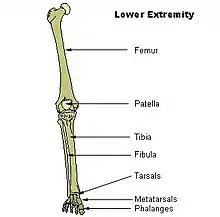

Fibular hemimelia or longitudinal fibular deficiency is "the congenital absence of the fibula and it is the most common congenital absence of long bone of the extremities."[1][2] It is the shortening of the fibula at birth, or the complete lack thereof. Fibular hemimelia often causes severe knee instability due to deficiencies of the ligaments. Severe forms of fibula hemimelia can result in a malformed ankle with limited motion and stability. Fusion or absence of two or more toes are also common.[3] In humans, the disorder can be noted by ultrasound in utero to prepare for amputation after birth or complex bone lengthening surgery. The amputation usually takes place at six months with removal of portions of the legs to prepare them for prosthetic use. The other treatments, which include repeated corrective osteotomies and leg-lengthening surgery (Ilizarov apparatus), are costly and associated with residual deformity.[4]

Characteristics are:

- A fibrous band instead of the fibula

- Short deformed leg

- Absence of the lateral part of the ankle joint (due to absence of the distal end of the fibula), and what is left is unstable; the foot has an equinovalgus deformity

- Possible absence of part of the foot requiring surgical intervention to bring the foot into normal function, or amputation.

- Possible absence of one or two toes on the foot

- Possible conjoined toes or metatarsals

Partial or total absence of fibula is among the most frequent limb anomalies. It is the most common long bone deficiency and is the most common skeletal deformity in the leg. It most often is unilateral (present only on one side). It may also present as bilateral (affecting both legs). Paraxial fibular hemimelia is the most common manifestation in which only the postaxial portion of the limb is affected. It is commonly seen as a complete terminal deficiency, where the lateral rays of the foot are also affected. Hemimelia can also be intercalary in which case the foot remains unaffected. Although the missing bone is easily identified, this condition is not simply a missing bone.[2] Males are affected twice as often as females in most series.[5]